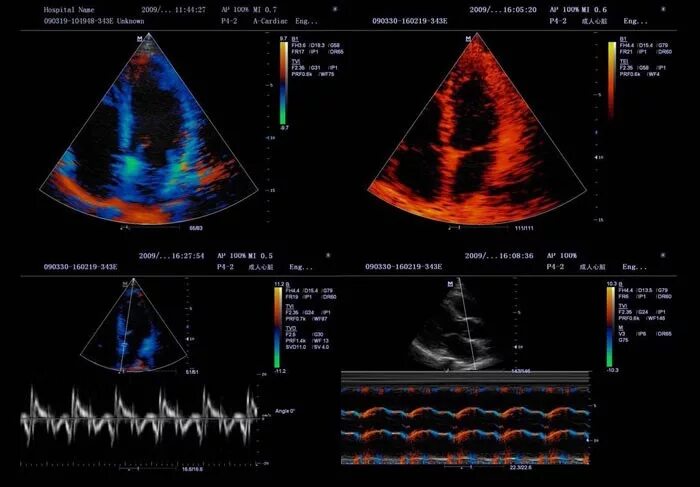

Узи сердца узи почек